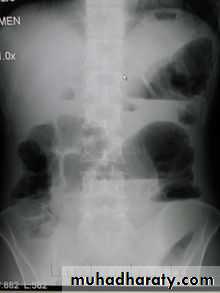

Intestinal gas pattern

Relatively large amounts of gas are usually present in the stomach and colon in a normal patient.The stomach can be readily identified by it's location, gastric rugae in the supine view , and by the air fluid level beneath the left hemidiaphragm in the erect view

The duodenum often contains air and show a fluid level

Short fluid levels in the small and large bowel are normal.